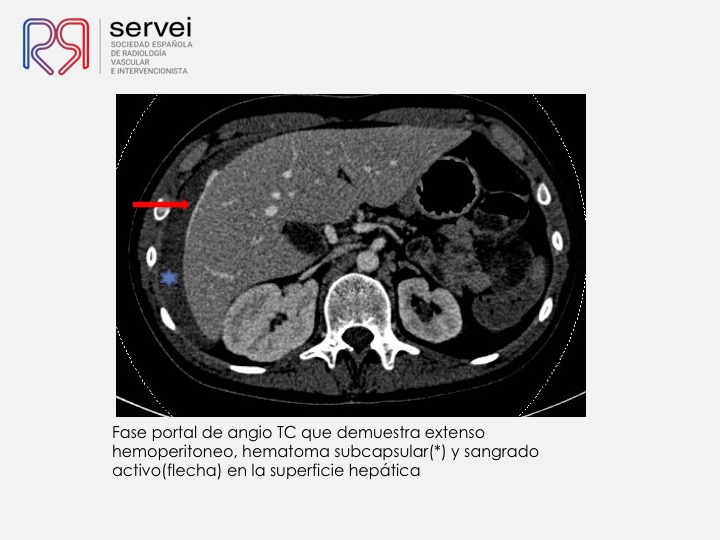

Una causa poco frecuente de hemorragia hepática postbiopsia, no sospechada, resuelta mediante embolización con Onyx por acceso transhepático